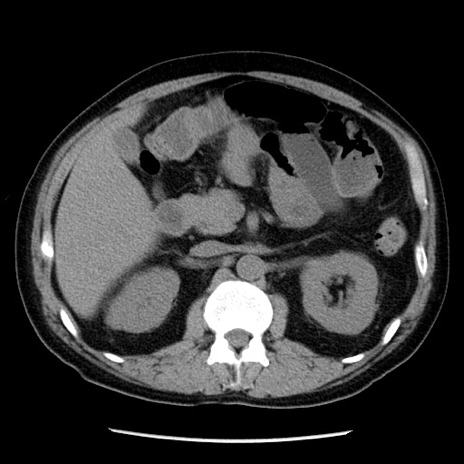

冠状断像

【症例】40歳代男性

【現病歴】2日前から胃痛あり。徐々に周期的な激痛に変化した。本日になっても激痛があるため受診。

【身体所見】意識清明、BT 38-39℃台あり、腹部:膨満、やや硬、右下腹部に圧痛あり。

【データ】WBC 8500、CRP 23.26